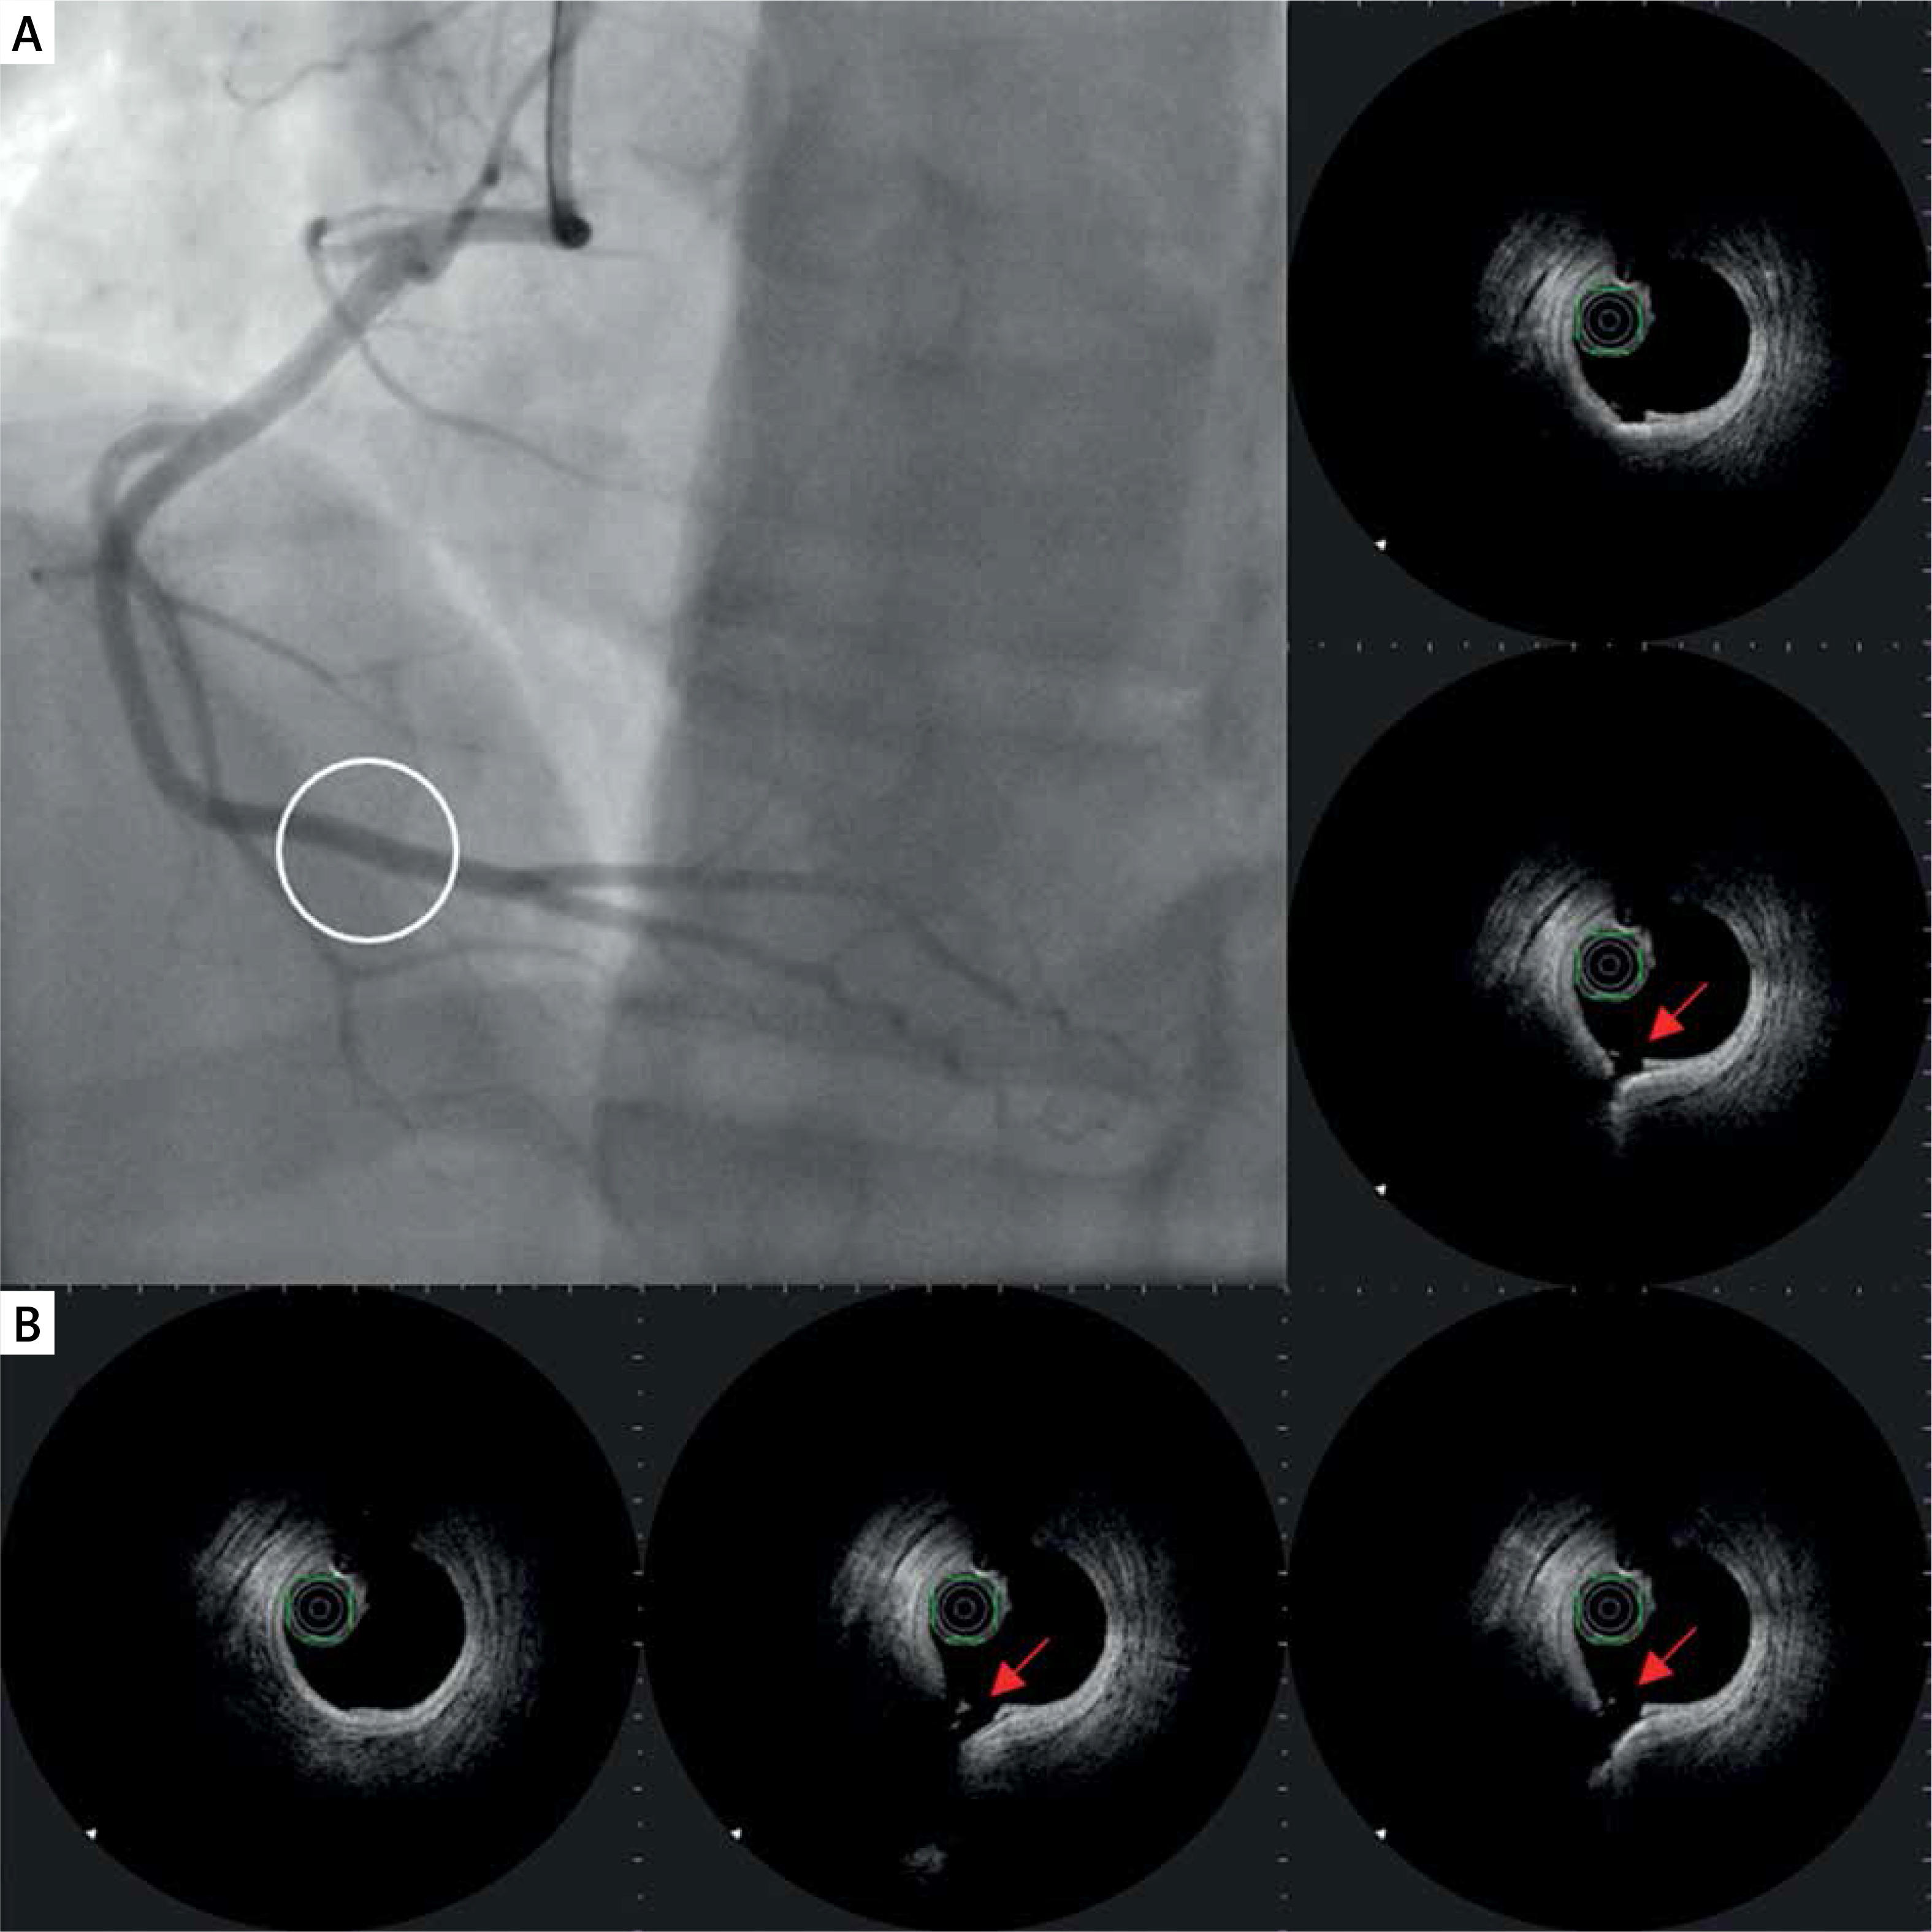

Plaque erosion

Another possible finding in the vessels is plaque erosion, defined as the presence of irregularly delineated thrombus masses located against the vessel wall that extend into the lumen without plaque rupture being visible in more than one adjacent cross-section (Figure 3). The thrombus appears non-homogeneous and is relatively bright due to the stronger reflection (white thrombus).